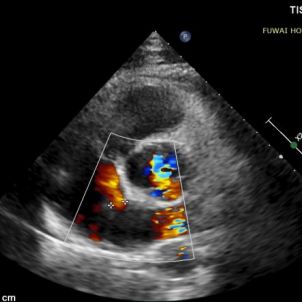

1-day postoperative TTE revealed that the occluder is in good shape without residual shunt (see last figure).